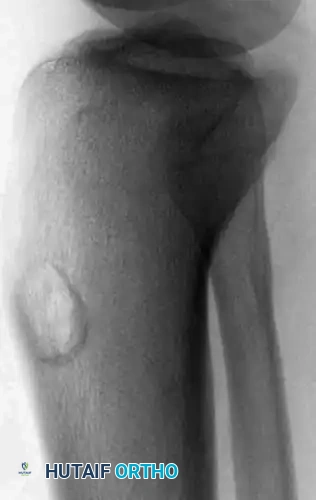

A 4-year-old boy with a 1-year history of right leg pain and antalgic gait. The right tibia was 2 cm longer than the left. Radiographs and CT reveal a lesion in the distal metaphysis causing bowing of the fibula, indicative of a chronic, benign process. The typical microscopic appearance confirms osteoblastoma.